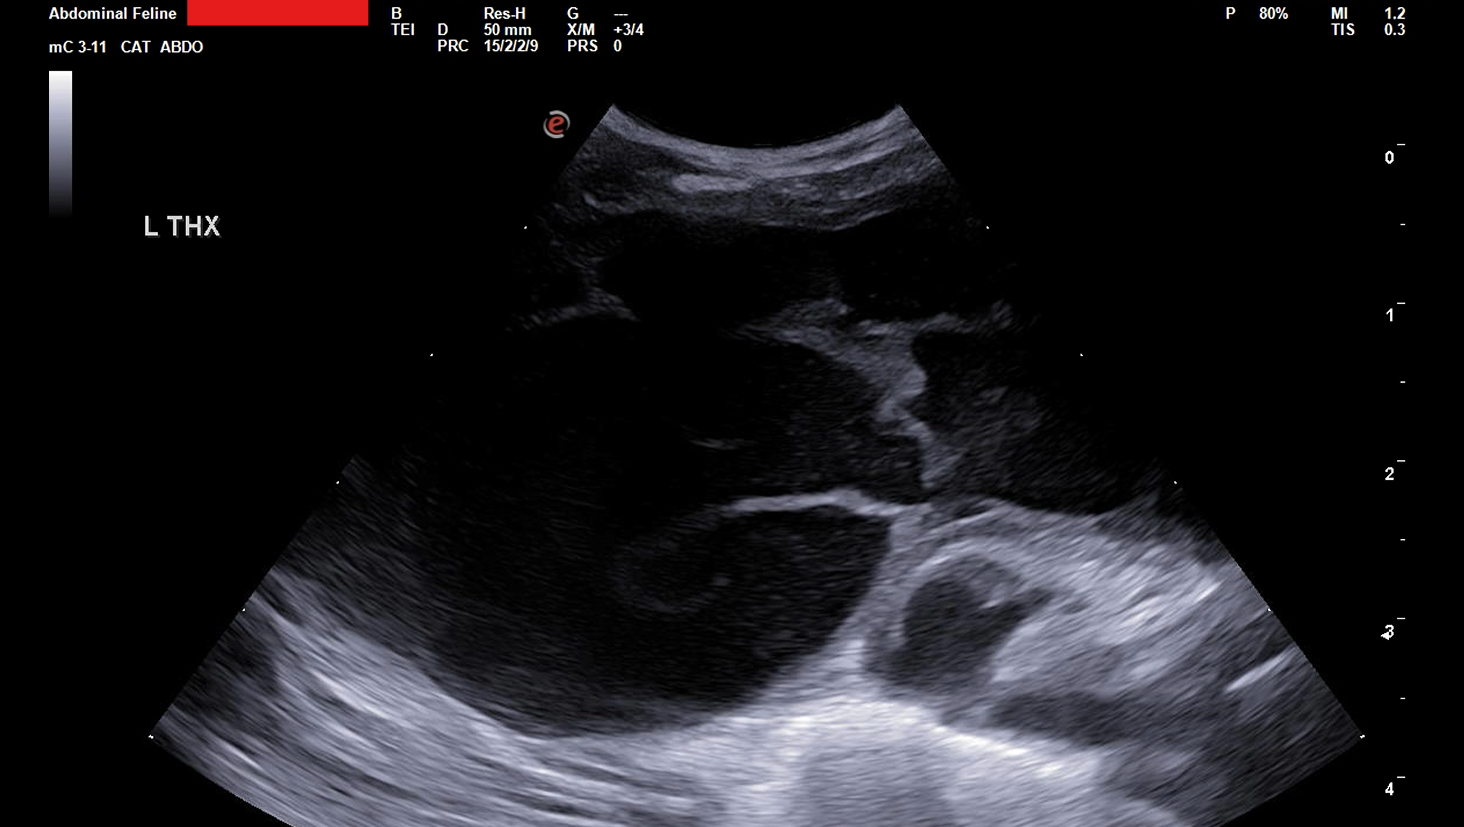

Mushashi suddenly became lethargic, stopped eating, lost weight, and struggled to breathe. He was rushed to the emergency vet, where tests revealed a massive buildup of fluid in his chest cavity (pleural effusion) that was preventing his lungs from fully expanding. The prognosis was grave.

After an emergency procedure to drain the fluid, Mushashi showed incredible resilience — but he is still in critical condition. His medical team now has a high suspicion for Feline Infectious Peritonitis (FIP), a rare and often fatal viral disease.